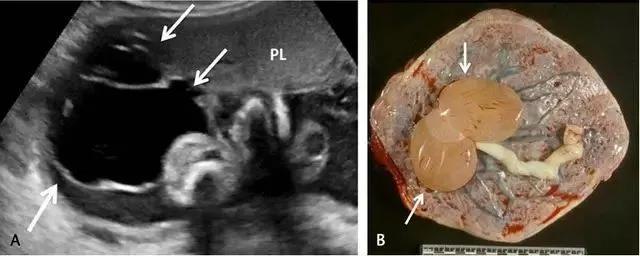

副胎盘

副胎盘是指一个或多个附属胎盘小叶通过血管与主胎盘相连,其发生率在所有妊娠中约占 5%~6%,在高龄孕妇及人工授精时发生率还会高一些。双胎盘是副胎盘的一个变异,其两叶胎盘的大小近似(图 4)。 在超声上,副胎盘表现为两个独立的胎盘通过脐带与主胎盘相连(图 5)

图 4 示足月双胎盘的大体病理标本,可见脐带起源于两叶胎盘的中间(箭头所示)

图 5 A 示孕 26 周的胎盘横切面,箭头示 2 个独立的胎盘小叶(长箭头),箭号指示二者之间可见脐带起源于此;图 B 为孕 34 周胎儿死亡后的胎盘大体病理标本,箭头示两个独立的胎盘由源自主胎盘的脐带相连接;该胎儿的死因是由于较大脐膨出导致脐带扭结、脐血管破裂

副胎盘应与一个胎盘附着于宫腔的两个部位相区别。需注意,子宫收缩可形似副胎盘,复查超声即可将二者区别开来。胎儿娩出后,副胎盘可因未被发现而滞留宫腔引起产后出血。副胎盘容易并发血管前置及帆状胎盘。